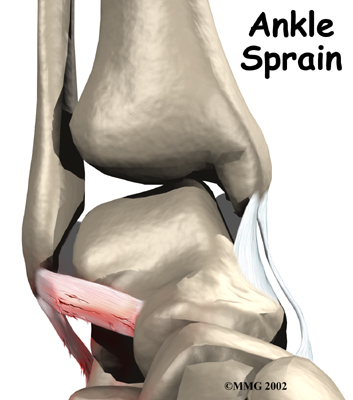

A ligament is made up of , similar to a nylon rope. A sprain results in stretching or tearing of the ligaments. Minor sprains only stretch the ligament. A tear may be either a complete tear of all the strands of the ligament or a partial tear of only some of the strands. The ligament is weakened by the injury; how much it is weakened depends on the degree of the sprain.

The lateral ligaments are by far the most commonly injured ligaments in a of the ankle. In an inversion injury the ankle tilts inward, meaning the bottom of the foot angles toward the other foot. This forces all the pressure of your body weight onto the outside edge of the ankle. As a result, the ligaments on the outside of the ankle are stretched and possibly torn.

Initially the ankle is swollen, painful, and may turn ecchymotic (bruised). The bruising and swelling are due to ruptured blood vessels from the . Most of the initial swelling is actually bleeding into the surrounding tissues. The ankle swells as extra fluid continues to leak into the tissues over the 24 hours following the sprain.

Initially the ankle is swollen, painful, and may turn ecchymotic (bruised). The bruising and swelling are due to ruptured blood vessels from the . Most of the initial swelling is actually bleeding into the surrounding tissues. The ankle swells as extra fluid continues to leak into the tissues over the 24 hours following the sprain.

People who have sprained an ankle often end up spraining the ankle again. If the ankle keeps turning in with activity, the condition is called ankle instability. Patients who have ankle instability lose confidence in their ankle to support them, especially on uneven ground. They often have swelling around the ankle that doesn't go away. Pain and swelling in a joint can cause a reflex where the body turns off the muscles around the joint. This can cause times when the ankle feels like it is going to give way, meaning it may have a tendency to twist again very easily.